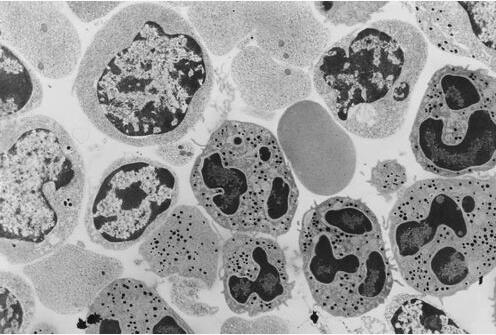

为计算人体内细胞的数量,德国马克斯普朗克研究所科学家通过分析1500多篇科学论文,确定了人体中有多少细胞类型、每个组织中有多少种细胞,以及每种细胞的平均大小和质量等因素。他们在60种不同的组织中发现了400多种已知的细胞类型。

研究结果表明,一名成年女性有28万亿个细胞;儿童有17万亿个细胞;成年男性有36万亿个细胞。研究还发现,无论是非常小的细胞、非常大的细胞还是大小介于两者之间的细胞的质量大致相同。